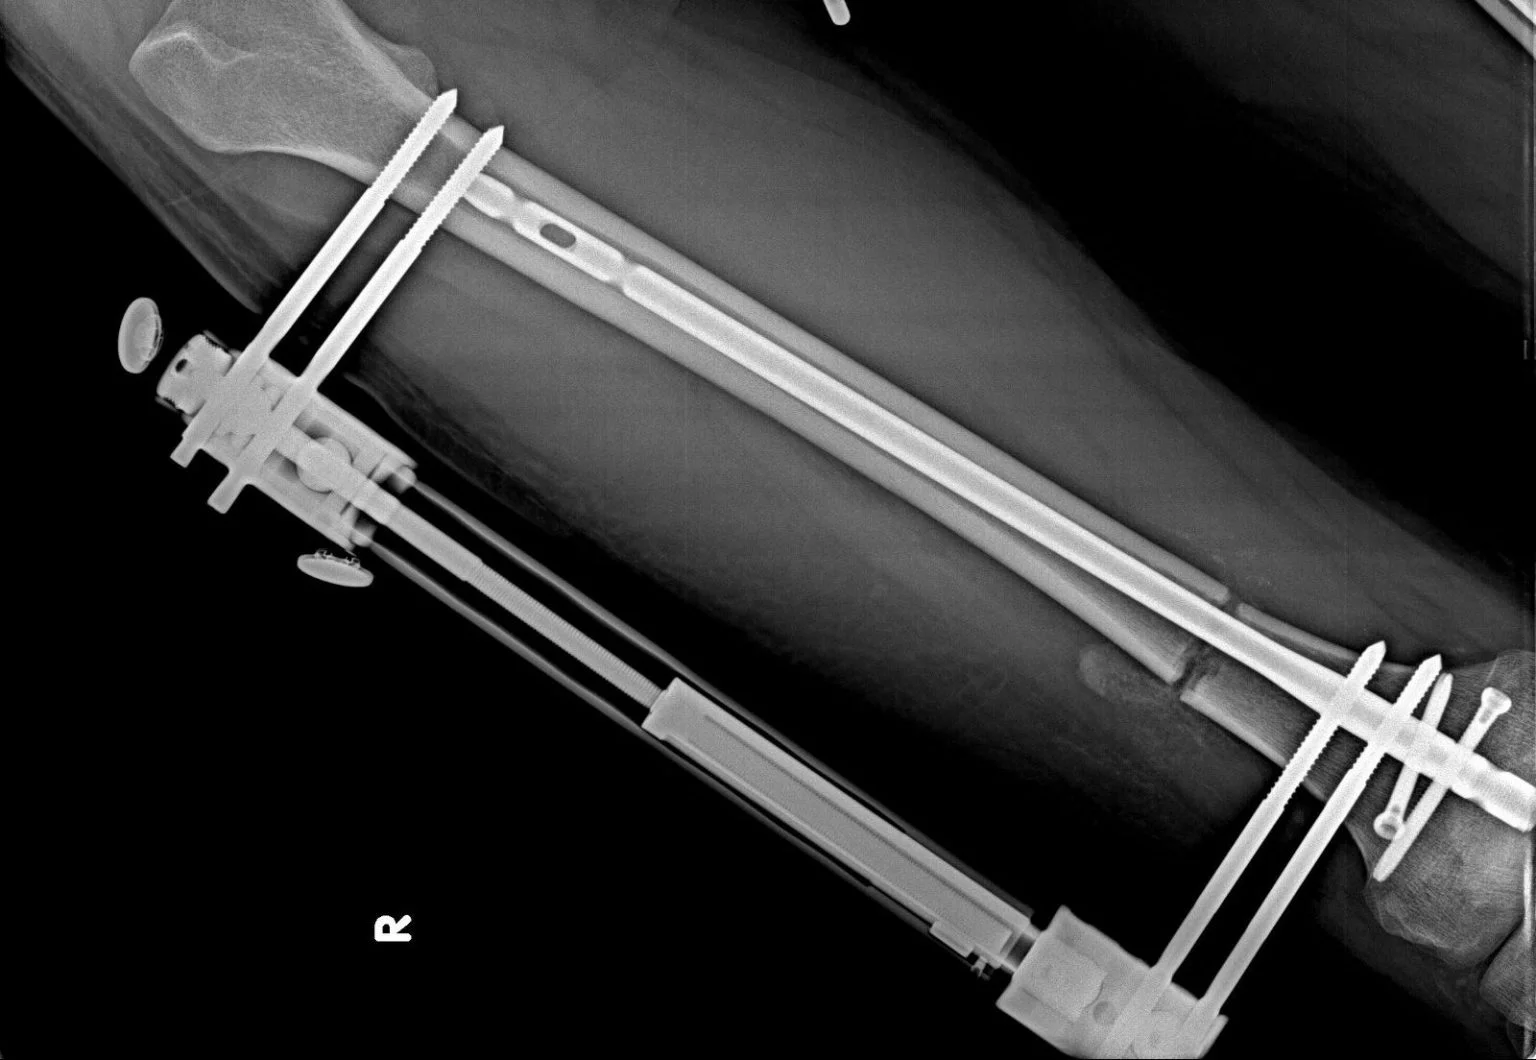

Los fijadores externos son estructuras fuertes que se utilizan en la cirugía de alargamiento de extremidades para sostener el hueso desde el exterior. Este dispositivo permite que los huesos se consoliden correctamente manteniéndolos inmóviles durante el proceso de alargamiento. Fabricado con varillas metálicas gruesas, el fijador se fija a los huesos mediante clavijas especiales, garantizando así un alargamiento seguro y controlado.

El fijador se coloca durante la cirugía y generalmente permanece en su lugar durante 2 a 3 meses, hasta que se logra el tamaño deseado. Durante este período, se asegura tanto el equilibrio óseo como un alargamiento sano y controlado.

Clavo intramedular;

Los clavos intramedulares son implantes de titanio biocompatibles que se utilizan para sostener el hueso y garantizar un alargamiento seguro durante las cirugías de alargamiento de extremidades. El tamaño de la uña lo determina el cirujano después de analizar las radiografías y generalmente varía entre 8,5 mm, 10,7 mm, 11,5 mm y 12,5 mm.

Insertado en el interior del hueso durante la cirugía, este clavo no causa ningún daño a los tejidos y no provoca ninguna reacción adversa gracias a sus propiedades biocompatibles.

Durante la operación, el hueso de la pierna (fémur para el muslo o tibia para la parte inferior de la pierna) se corta cuidadosamente en un punto predefinido. Este corte controlado permite que el hueso se alargue gradualmente a partir de entonces. Se inserta un clavo intramedular en el hueso y se fija un fijador externo en el exterior para asegurar la correcta curación del hueso y un alargamiento seguro.